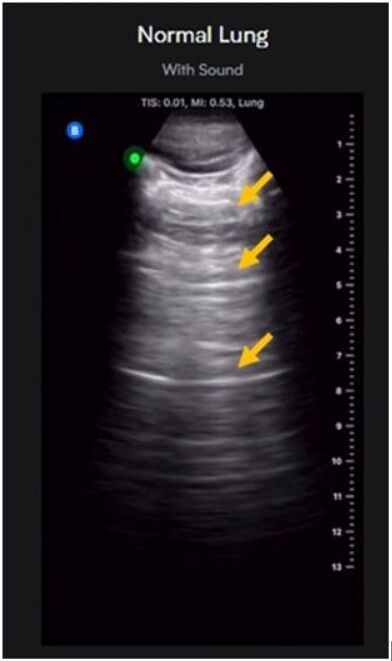

26.利用超音波影像進行肺炎篩檢,如圖為正常肺部影像,其影像中箭號處所指之影像假影為何?

(A)加強(enhancement)假影

(B)殘響(reverberation)假影

(C)範圍模糊(range ambiguity)假影

(D)閃爍(flash)假影

箭頭指的是一條一條相等間隔的橫線延伸 所...

這題的正確答案是 (B) 殘響 (re...